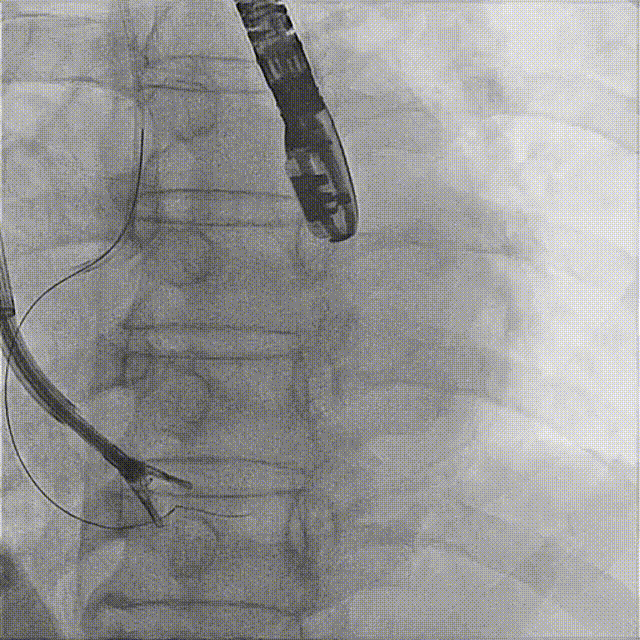

7. Coronary artery course and blood supply were evaluated under DSA (the course of the coronary artery was altered, but blood supply remained normal).

The first clip was initially implanted at the posterior‑septal commissure, which resulted in deformation of the coronary artery course. The first clip was released and repositioned toward the septal leaflet, with the clip arms opened to cross the posterior‑septal commissure before re‑implantation.

Initial DSA after clipping indicated compromised blood supply. The clip was therefore released, repositioned, and redeployed.